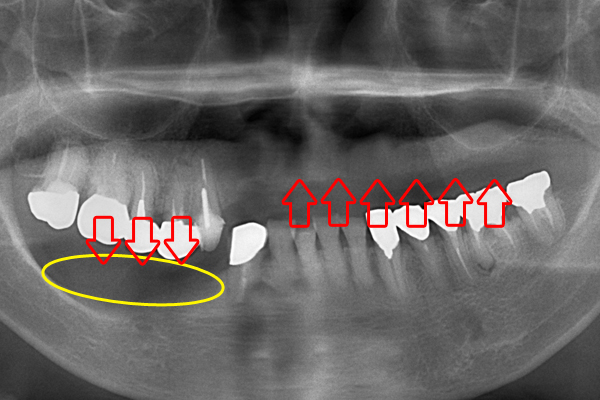

入れ歯(義歯)の種類

金属床義歯

治療期間:1ヶ月半、通院回数:5回

価格:30万円(税別)

- 治療内容

- 薄くて壊れにくい義歯を希望したため金属床義歯を作成。型を精密に2回取り、かみ合わせの確認や見た目の確認などを経た上で装着。

- リスク

- 保険の義歯に比べ費用がかかる。アレルギーの場合に適応できないことがある。

装着前

装着後